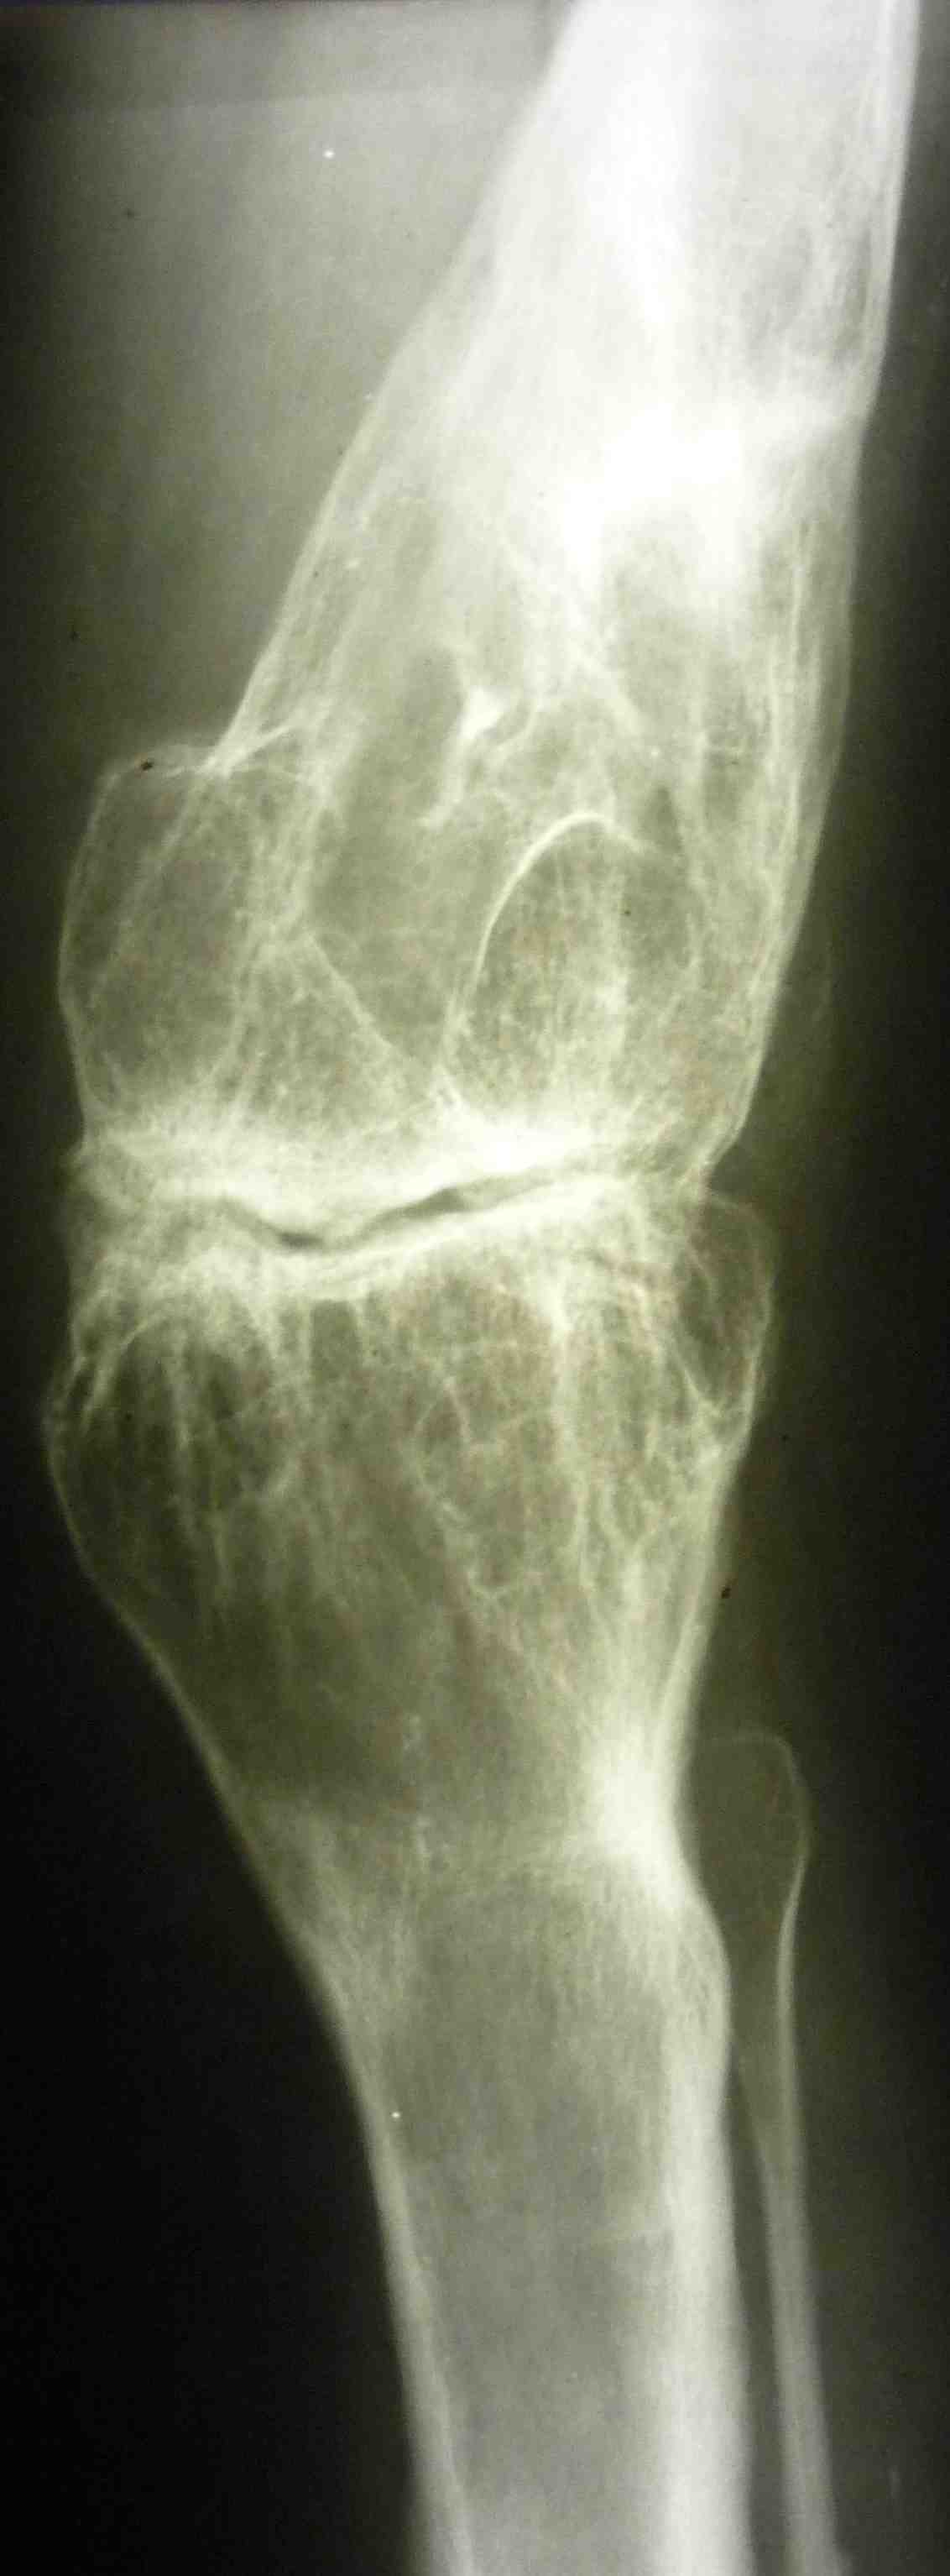

[Ortho] эндопротезирование коленного сустава

В настоящее время нет возможности сделать осевые снимки всей конечности.

Это всё чем я раполагаю на сегодняшний день.